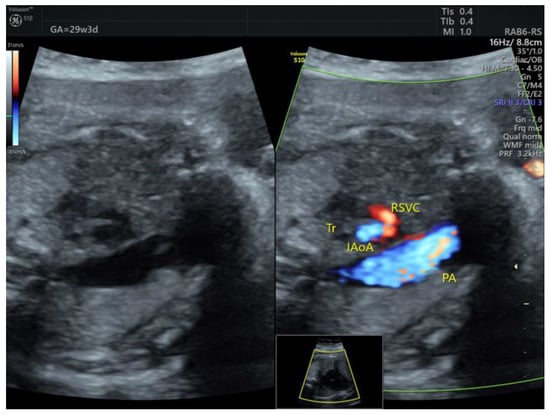

| IAoA | 1 | perimembranous VSD | - | 3VT | + | 0 | 1 | 0 | 1/1 |

| DAA | 1 | Tortuous DA at 20 w + late FGR | - | 3VT | + | 0 | 0 | 1 | 1/1 |